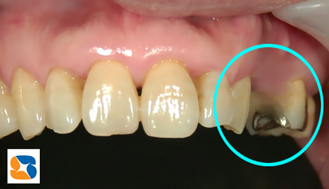

この写真は、右上に、3本のインプラント治療が完成したところです。50代の女性。主訴は「私、どうしても入れ歯は馴染めないわ。思いきってインプラントしようかしら?」でした。

金属部分=写真=が、歯茎から少し出ているのが分かりますか?

これから、この部分に白いセラミックの歯を取付けていきます。